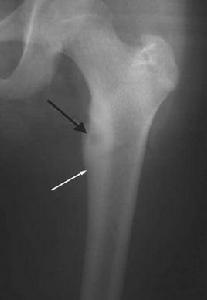

X線表現 :骨樣骨瘤的影像學表現多具特徵性,瘤巢的確定是診斷骨樣骨瘤的關鍵。瘤巢一般位於病變中心,常為單個瘤巢,偶見2個以上的瘤巢。半數以上巢內發生鈣化或骨化,形成“牛眼征”。瘤巢周圍硬化廣泛時,可以遮蔽瘤巢,此時用體層攝影或CT掃描才能顯示瘤巢。